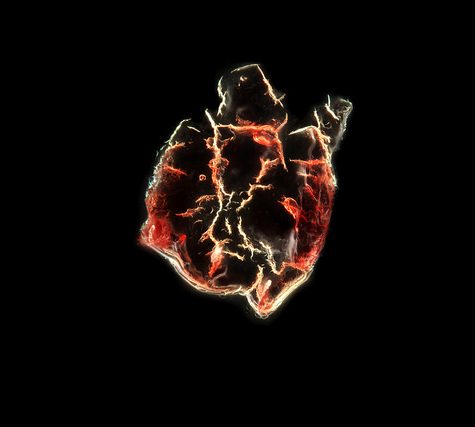

A thrombus, colloquially called a blood clot, is the final product of the blood coagulationstep in hemostasis. There are two components to a thrombus: aggregated platelets and red blood cells that form a plug, and a mesh of cross-linked fibrin protein. The substance making up a thrombus is sometimes called cruor. A thrombus is a healthy response to injury intended to prevent bleeding, but can be harmful in thrombosis, when clots obstruct blood flow through healthy blood vessels.

A thrombus, colloquially called a blood clot, is the final product of the blood coagulationstep in hemostasis. There are two components to a thrombus: aggregated platelets and red blood cells that form a plug, and a mesh of cross-linked fibrin protein. The substance making up a thrombus is sometimes called cruor. A thrombus is a healthy response to injury intended to prevent bleeding, but can be harmful in thrombosis, when clots obstruct blood flow through healthy blood vessels.